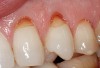

Figure  9  A Class V non-carious cervical lesion.

Figure 9

Figure  10  The Class V lesion restored with self-adhesive resin-based composite.

Figure 10